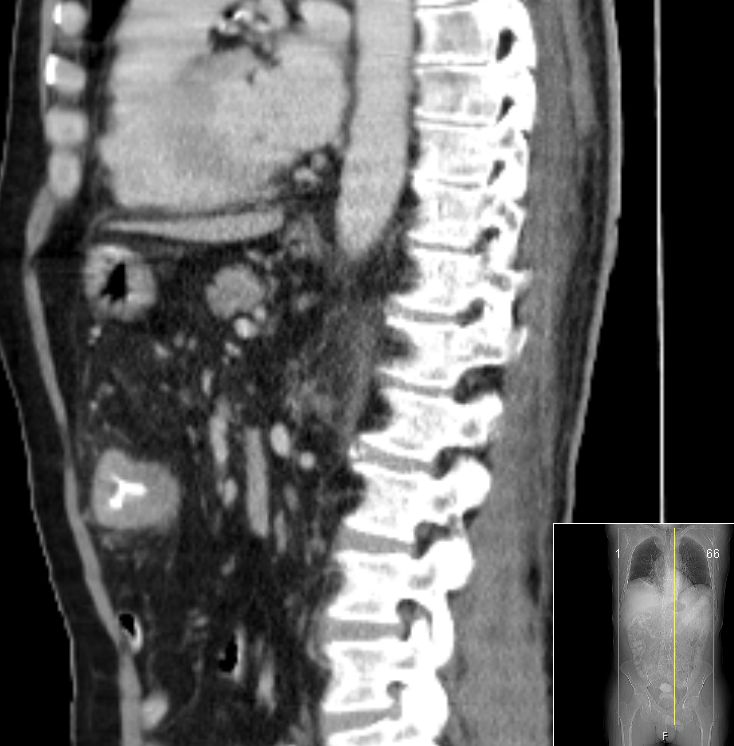

| Colon ascendens | 7-jährige Frau mit Colon ascendes Tumor pT3d pN2a(4/20) L1 Vo.

Großer Tumor mit Infiltration des Fettgewebes. Kein Ileus! |